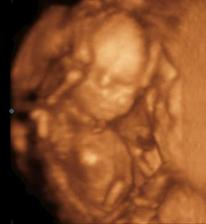

zulka29

30. jan 2009

Naše babuliatko